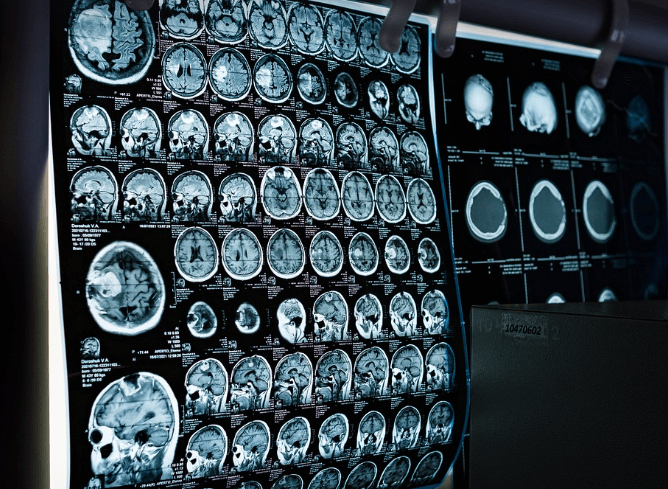

퇴행성관절염 치료방법, 어떻게 해야 할까?

퇴행성관절염은 현재로서는 완치보다는 ‘증상 완화와 진행 억제’가 치료의 핵심입니다.

증상 정도에 따라 다음과 같은 방법들이 사용됩니다.